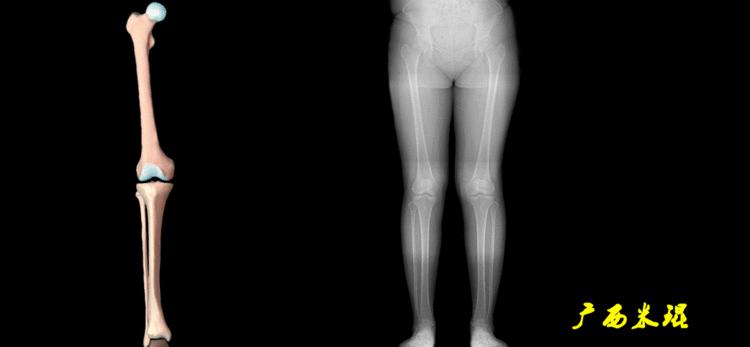

2、画出下肢的轴线

确定髋关节、膝关节、踝关节的中心点后,我们才能了解下肢的几个轴线。

(1)解剖轴

股骨和胫骨的骨干中线为解剖轴,股骨解剖轴和胫骨解剖轴的夹角正常值为174°±1°。

(2)机械轴

机械轴是连接近端和远端关节中心点的直线。

机械轴要分前后位及侧位,站立前后位(也就是冠状面)股骨头中心与踝关节中心的连线通过膝关节中心,这是下肢的机械轴线,也就是下肢力线,常说Mikulicz线。冠状面的力线评估在临床工作中最常用、最基础、最重要。